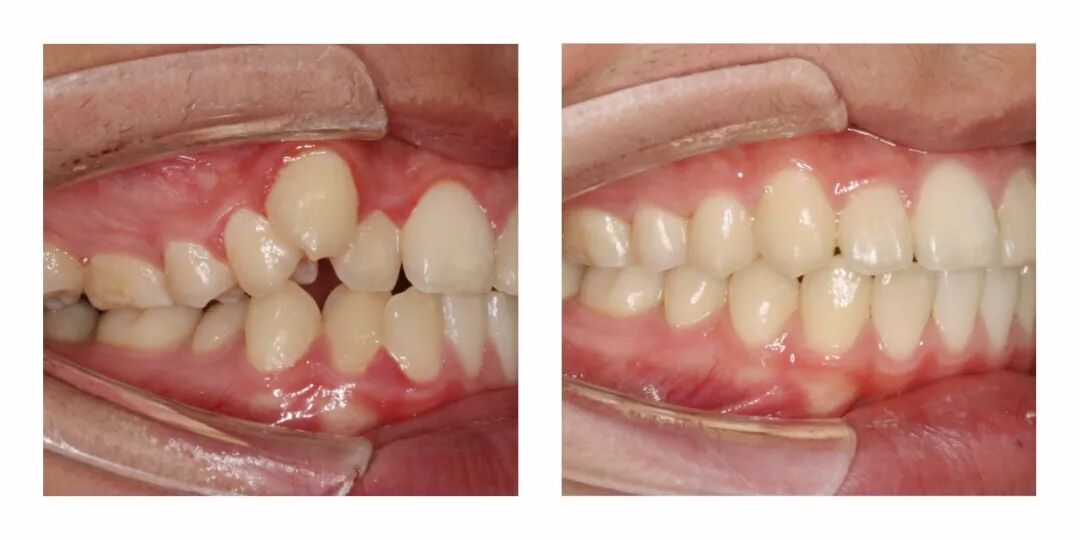

他家有一些具体的正畸案例,效果也很惊人。▼

感觉虽然只是矫正了牙齿,但是整体颜的感觉都不一样了有木有?

从苹果肌到鼻子的形状、下巴的线条,都完全变了啊……▼